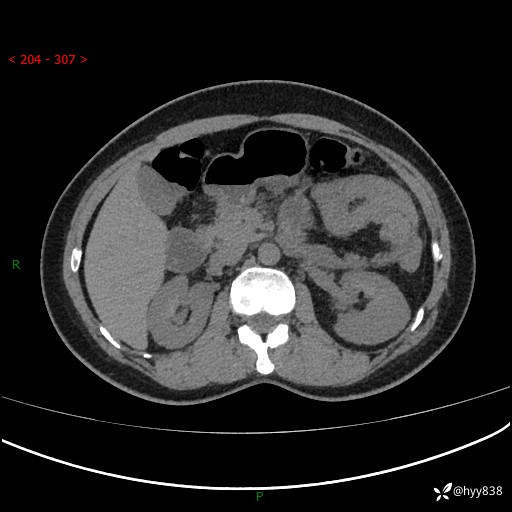

现病史:患者1天前无明显诱因下出现左上腹部及腰背部胀痛不适,阵发性加剧,伴肛门停止排气;无发热,无恶心呕吐,无畏寒发热,无心慌气短等不适,于当地市第二人民医院就诊,行腹部ct检查提示左上腹区肠系膜血管从剧聚集,分布紊乱伴肠管局限性稍扩张积液,不完全性肠梗阻;考虑子宫颈纳氏囊肿,双侧附件区囊状灶;予以抗炎及对症支持等治疗后未见明显缓解,现患者为求进一步治疗来我院急诊就诊,遂以“肠梗阻”收住入院。 病来,神志清,精神可,饮食睡眠不佳,经灌肠后排便2次,小便正常,体力体重无明显变化。

上腹部CT平扫